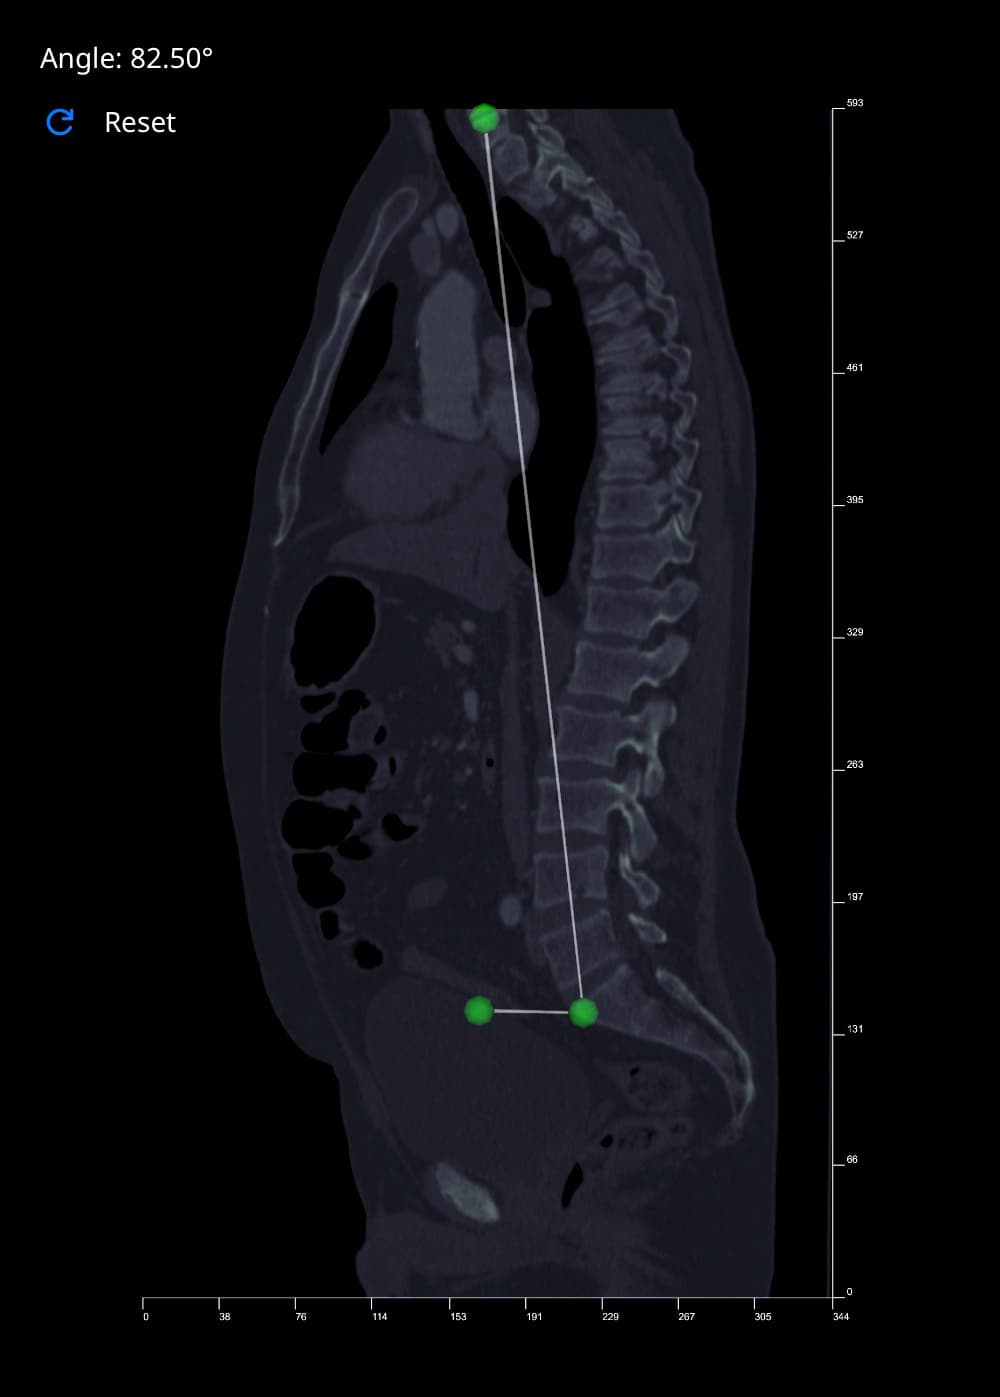

Measure Angle Tool

This tool works by calculating the angle between three points that you place on an image. The second point acts as the vertex, with the first and third acting as the arms of the angle. Follow the steps below to create an angle measurement:

- Select the 'Measure Angle' button. Vista will reduce the opacity of the image in view by half, to make your placement of points more visible and accurate.

- Move your cursor over the image, and left-click to place a point. As you hover over an image, a blue polygon will follow your cursor, giving you an indication of where your point will be placed. Once selected, the polygon will turn green.

- Repeat this process two more times to create the initial side, vertex and terminal side of the angle.

- Once complete, the 'Angle' label at the top-left of the Rendering Canvas will be updated with the measurement.

If you want to start again, click the Reset button to clear the Angle. When you are done, de-select the 'Measure Angle' button to deacivate this tool.

The left image above shows examples of angle measurements in full-length spine radiographs. The image to the right shows a Spinal Tilt angle measurement taken on a CT Scan in Vista.